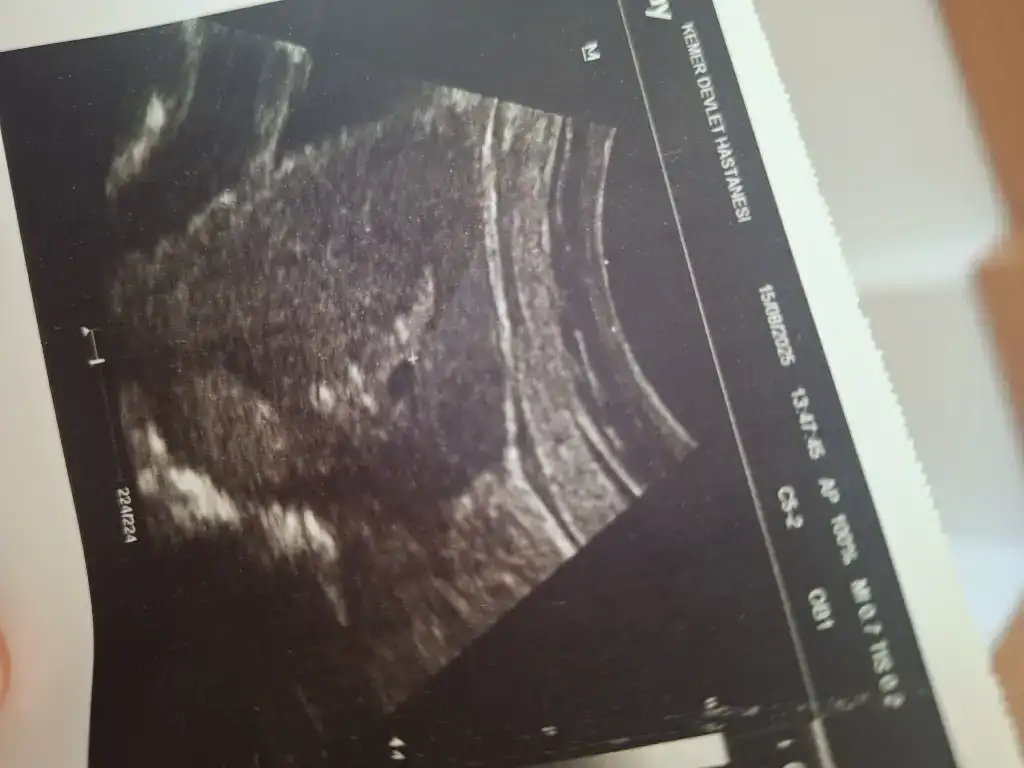

Ayyy maşallah ya nasıl güzel bir haber bu allahım nolur bende sevincimi yazayım bu ay burayaKızlar nasılsınız. Kaç gündür giremedim hiç buraya dün arkadaşım doğum yaptı sürekli onunla ilgilendik. Bugünde Dr randevum vardı. Gittim Dr a kese falan görünmeyeceğine emindim. Ama Dr önce ultrasonla bakalım dedi vee teyzeleri bebeğim minik kesesi gözüktü. Nasıl mutlu oldum anlatamam. Düzensiz adet olduğum ve kese küçük olduğu için tam hafta veremedi. İnaşşalah kalp atışlarını da duymak nasip olur. Bude minik kesemiz bir maşşalah alırız.

Ayyy Allah ımm Maşallah Rabbim kalp atışlarını duymayı sağlıkla kucağınıza almayı da nasip etsinKızlar nasılsınız. Kaç gündür giremedim hiç buraya dün arkadaşım doğum yaptı sürekli onunla ilgilendik. Bugünde Dr randevum vardı. Gittim Dr a kese falan görünmeyeceğine emindim. Ama Dr önce ultrasonla bakalım dedi vee teyzeleri bebeğim minik kesesi gözüktü. Nasıl mutlu oldum anlatamam. Düzensiz adet olduğum ve kese küçük olduğu için tam hafta veremedi. İnaşşalah kalp atışlarını da duymak nasip olur. Bude minik kesemiz bir maşşalah alırız.